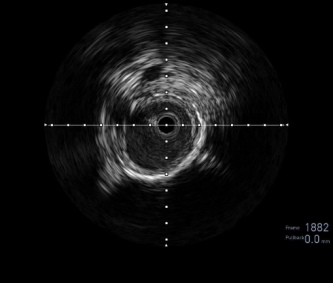

图:LA 基线造影

图:IVUS测量

图:Auryon Atherectomy System-减容

图:DCB扩张后的全程造影